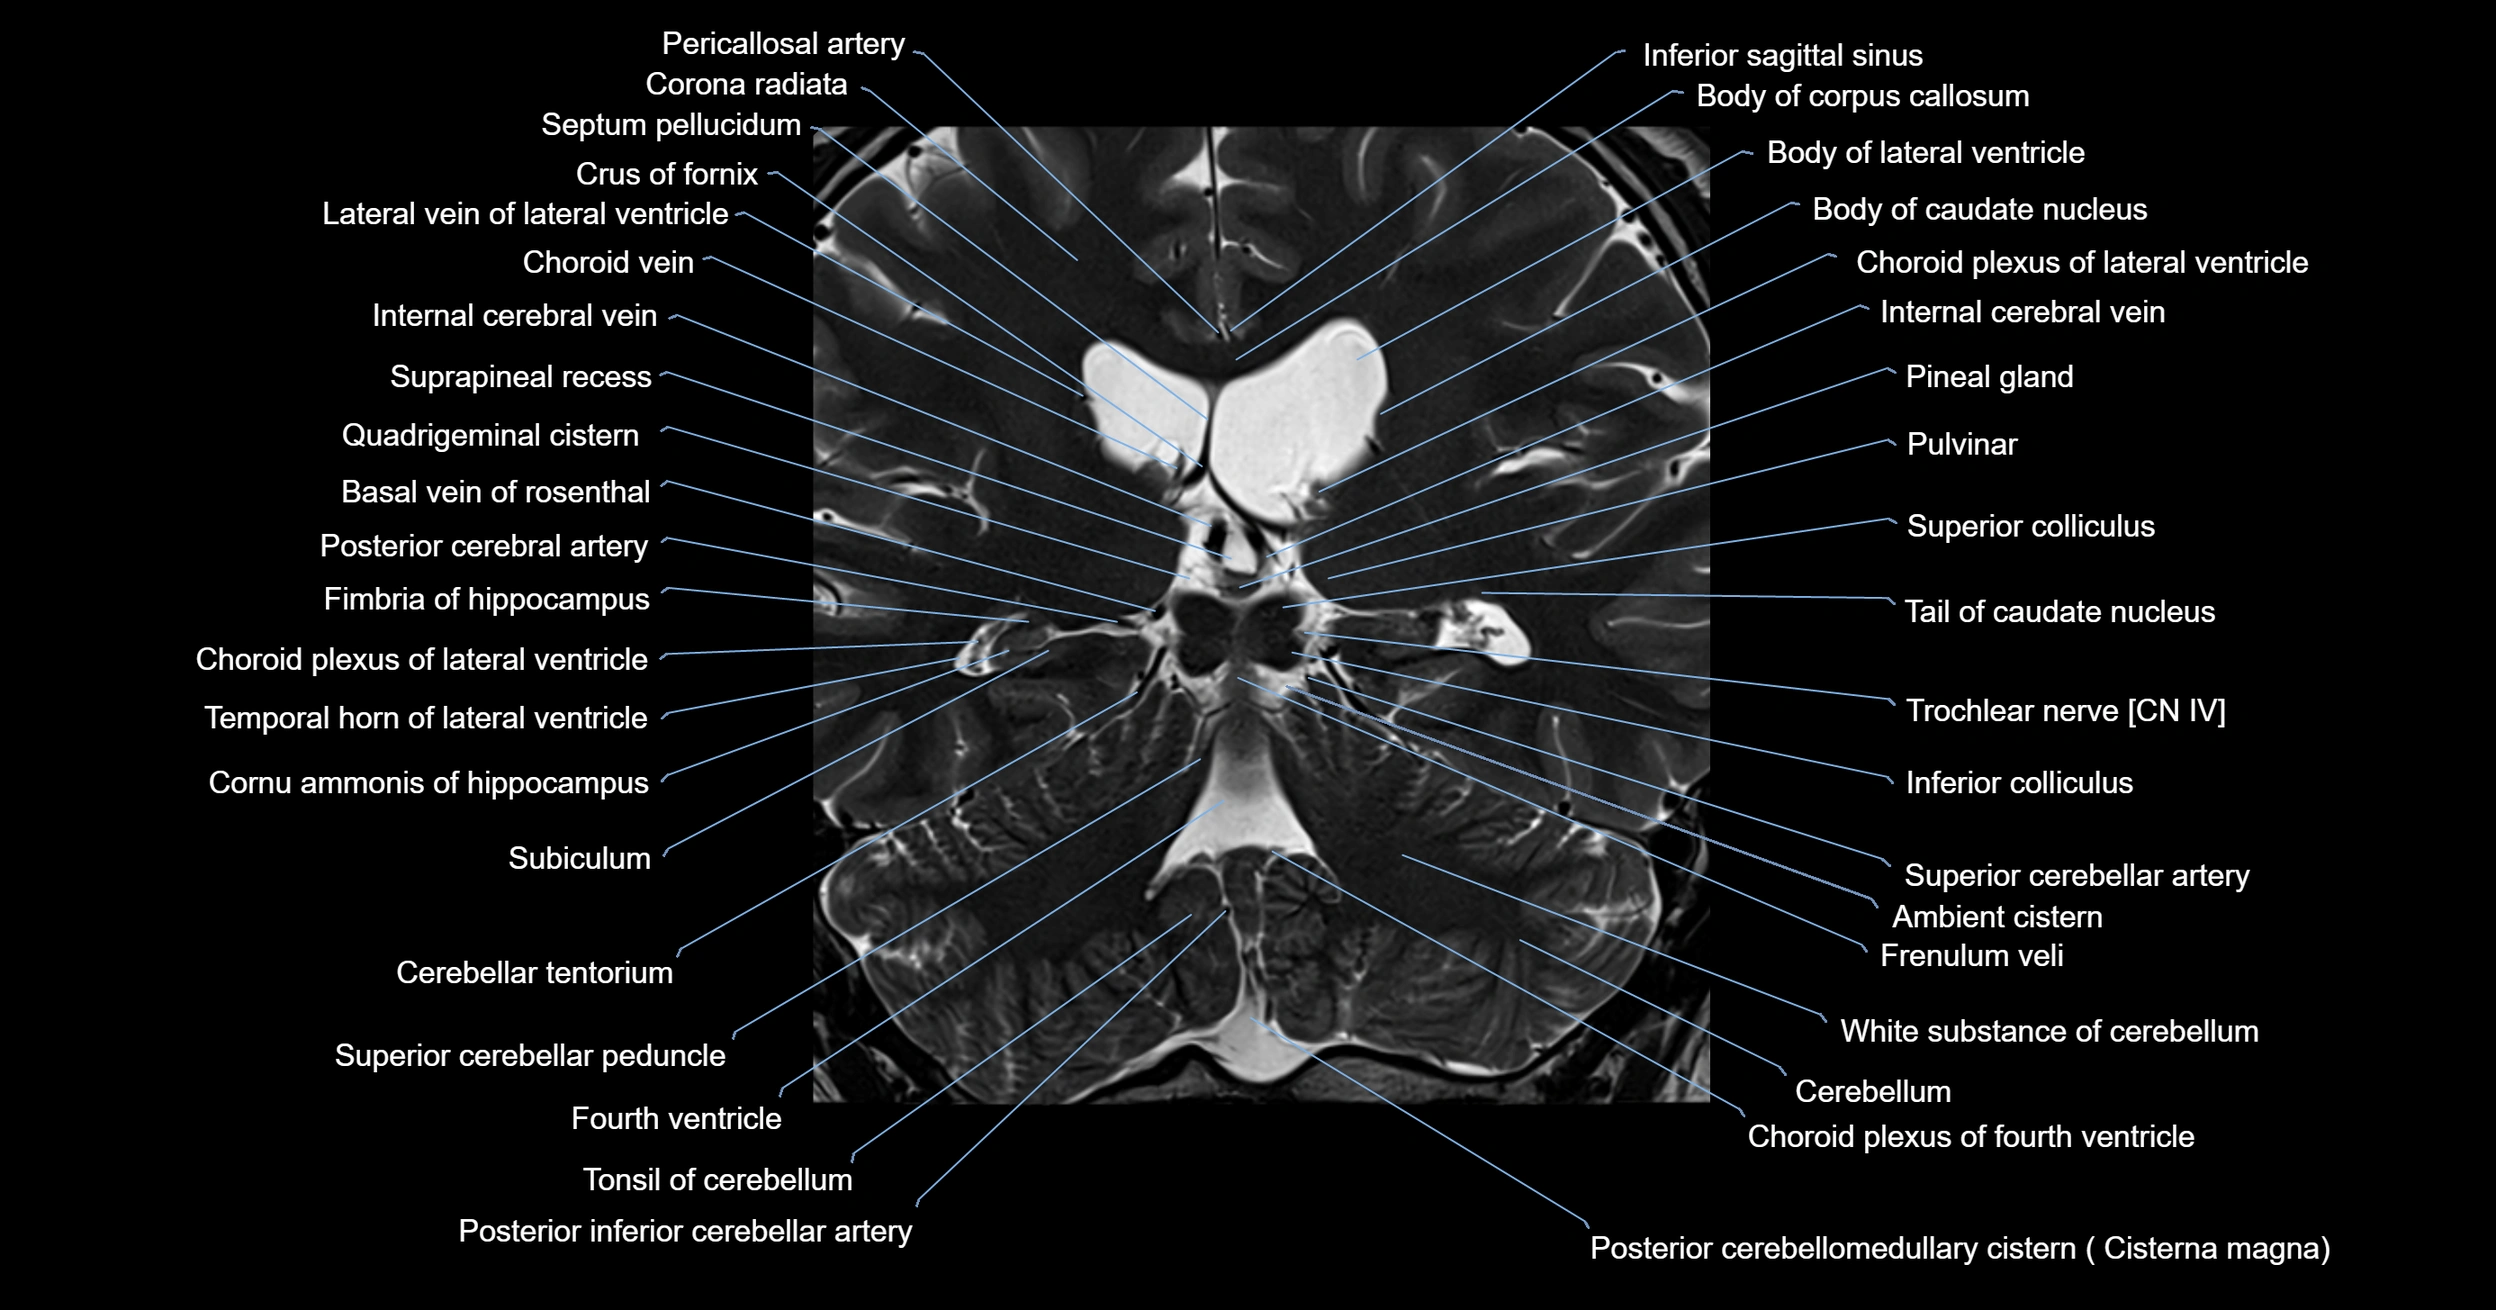

- Ambient cistern

- Basal vein of rosenthal

- Body of corpus callosum

- Body of lateral ventricle

- Cerebellar tentorium

- Cerebellum

- Choroid plexus of fourth ventricle

- Choroid plexus of the lateral ventricle

- Crus of fornix

- Fourth ventricle

- Frenulum veli

- Inferior colliculus

- Inferior sagittal sinus

- Pineal gland

- Posterior cerebellomedullary cistern (cisterna magna)

- Posterior cerebral artery (P1 Segment)

- Posterior inferior cerebellar artery

- Pulvinar

- Quadrigeminal cistern

- Superior cerebellar peduncle

- Superior colliculus

- Superior vein of vermis

- Suprapineal recess

- Tail of caudate nucleus

- Temporal horn of lateral ventricle

- Tonsil of cerebellum

- Trochlear nerve (Cranial nerve IV)